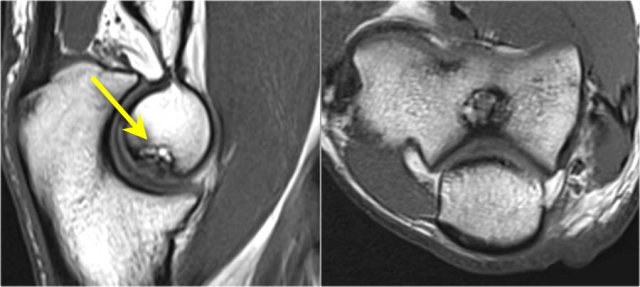

Pseudo-loose body

Another common finding is a small piece of fat that you'll see on the sagittal image, that looks like a small loose body or a cartilage defect.

This can be explained if we look at the articular surface of the olecranon.

Typically the olecranon has two pieces of cartilage with a small area inbetween, that fills with fat.

Plica

This structure on the lateral side of the joint is sometimes seen and is a plica.

It can be prominent and almost look like a meniscus.

It is a normal structure, but sometimes it is thickened or irregular and it may be a cause of symptoms.